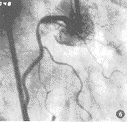

众多学者认为:冠心病冠脉病变以左前降支最多见,其次是右冠及回旋支(图1,2),本组病变左前降支占49.6%,右冠28.5%,回旋支20.3%,而左主干仅有6例,与文献[1,2]报道相一致。

图1 左前降支起始部,回旋支中段局限性偏心重度狭窄